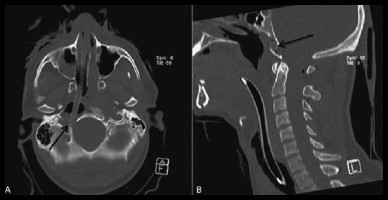

Fracture de Jefferson au niveau de l’arc antérieur C1 (première vertèbre) et élargissement du canal rachidien secondaire à la fracture de l’arc antérieur de C1.

Les radiographies peuvent détecter plusieurs fractures cervicales, telle que la fracture de Jefferson au niveau de la deuxième vertèbre. Ce type de fracture crée une ouverture de l’anneau de la première vertèbre et, en conséquence, un élargissement du canal rachidien (conduit à l’intérieur de la moelle épinière). Il est possible de voir une entorse grave des deux premières vertèbres. Ce trauma est souvent lié à une hyperflexion du cou, ce qui donne lieu à une lésion du ligament transverse empêchant un frein postérieur. Une partie de la première vertèbre cervicale se déplace alors vers l’arrière et comprime le canal spinal. Il est donc possible de voir, sur une radio de profil, le déplacement de l’arc antérieur de C1 et la face antérieure de l’odontoïde.

Coupe coronale (plan de droite à gauche) de la colonne cervicale montrant des éclats de vitre dans l’oesophage masqués par le tube endotrachéal (cathéter inséré dans la trachée).

Coupe sagittale (symétrique) de la colonne cervicale montrant des éclats de vitres dans l’oesophage masqués par le tube endotrachéal.